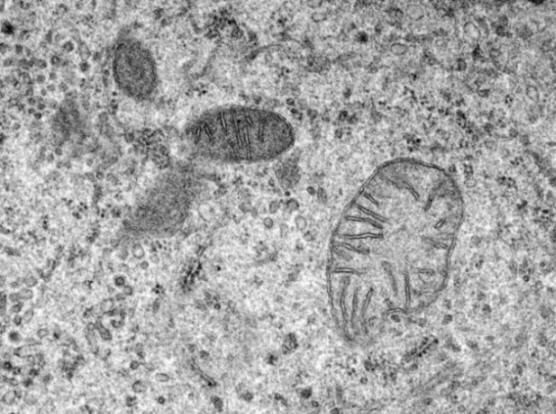

8. Kako delujejo mitohondrije?

Mitohondrije so sestavni del našega telesa. Edini namen mikroskopskih organelov je preoblikovanje vseh hrana, ki jo zaužijemo v energijo. Zelo dolgo nismo vedeli mitohondrije skoraj nič, a znanost je blizu razumevanja, kako delajo.

Pred kratkim so znanstveniki izvedeli, kako mitohondriji prenašajo energijo. Znanstveniki so prav tako izvedeli, da mitohondriji resnično potrebujejo kalcij oz. kar lahko včasih povzroči težave: če se mitohondriji absorbirajo preveč kalcija, lahko ubije celice. To je posledica bolezni, kot je diabetes tipa 2.

Raziskovalci verjamejo, da te bolezni vplivajo postopek oddajanja signalov, preko katerega telo komunicira mitohondrije, koliko kalcija se absorbira in koliko se izloči. Pred kratkim je uspelo pripeljati raziskovalno skupino s Harvarda katalogizirajte vsak protein v mitohondrijih, vključno z vsemi proteini, povezana z absorpcijo kalcija. Zaenkrat je malo informacij, vendar to bomo rešili skrivnost.